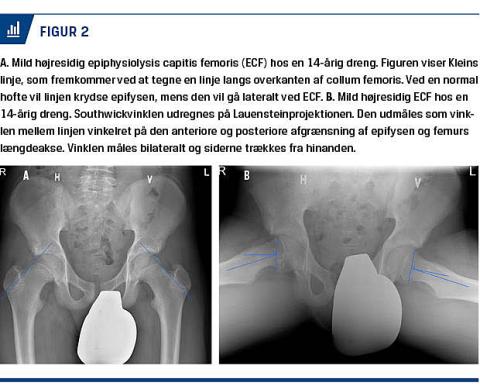

ECF kan diagnosticeres radiologisk ved anterior-posterior (AP)-optagelse af bækken og hofte samt med patienten i frøstilling, den såkaldte Lauensteinprojektion. Lauensteinprojektionen er velegnet til diagnosticeringen, men er ikke standardlateraloptagelsen overlegen [19, 20]. På AP-optagelsen kan diagnosen stilles vha. Kleins linje (Figur 2A og Figur 3A) [14, 21], som dog ved den milde og moderate ECF har lav sensitivitet, hvorfor Lauensteinprojektionen eller lateraloptagelsen altid skal tages [19].

Sværhedsgraden kan bl.a. beskrives ved Southwickvinklen, som måles på Lauensteinprojektionen og

inddeles i mild, moderat og svær. Udmåling af Southwickvinklen fremgår af Figur 2B. Under 30 grader kategoriseres som mild, 30-50 grader karakteriseres som moderat og over 50 grader karakteriseres som svær (Figur 3B). Klassifikationen af sværhedsgraden er af betydning, da mild og moderat ECF har en bedre langtidsprognose end svær ECF [6, 14, 19]. CT er ikke røntgenundersøgelse overlegen i diagnosticeringen [14], mens MR-skanning er mere sensitiv end røntgen og CT, men ikke bruges rutinemæssigt. MR-skanning kan desuden bruges til undersøgelse af vaskulariseringen af epifysen præoperativt og anbefales derfor af nogle som et vigtigt prognostisk værktøj [13, 22].